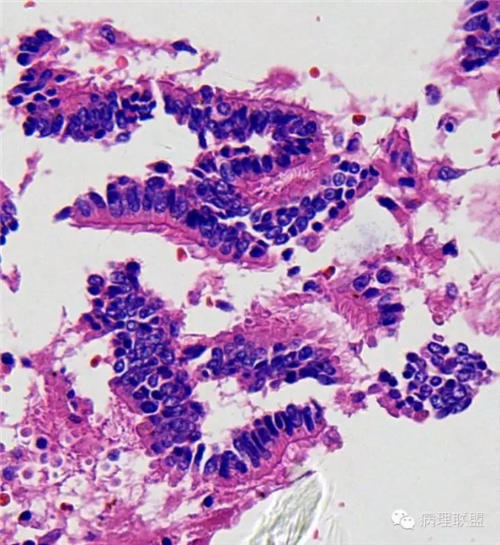

肺的

不仅仅是肺水肿